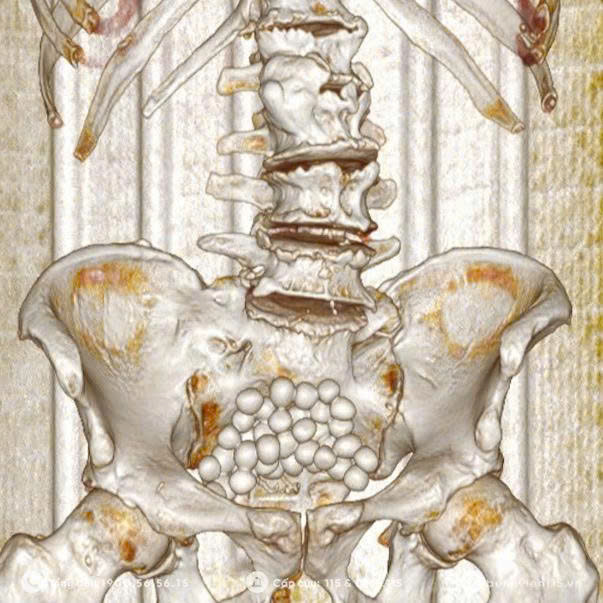

Qua siêu âm và chụp Cắt lớp vi tính bụng – tiểu khung cho kết quả thành bàng quang dày không đều, có túi thừa và nhiều sỏi bàng quang. Bác sĩ chuyên khoa Ngoại Tổng hợp đã đưa ra phương án phẫu thuật mở bàng quang lấy sỏi, cắt túi thừa bàng quang.